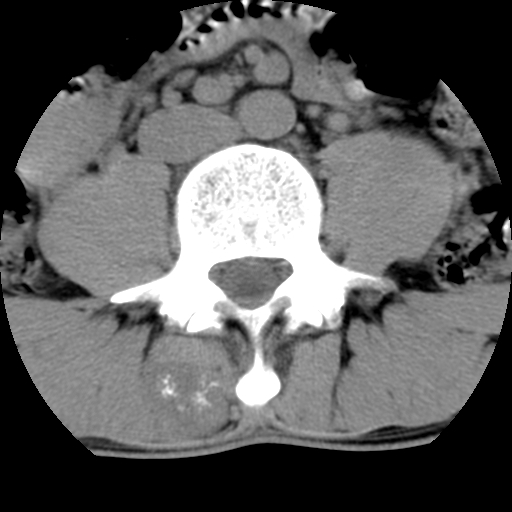

标题: CT16890:男,腰背痛.

男,腰背痛

本人诊断1tb2包虫,请会诊

1)右侧竖脊肌稍低密度肿块伴钙化(性质待定),不排除肿瘤可能;建议行进一步检查。2)腰椎间盘突出。

1.右侧竖脊肌软组织肿块伴团块状钙化,首先考虑血管瘤可能性大;建议行进一步检查;2。腰椎间盘突出。